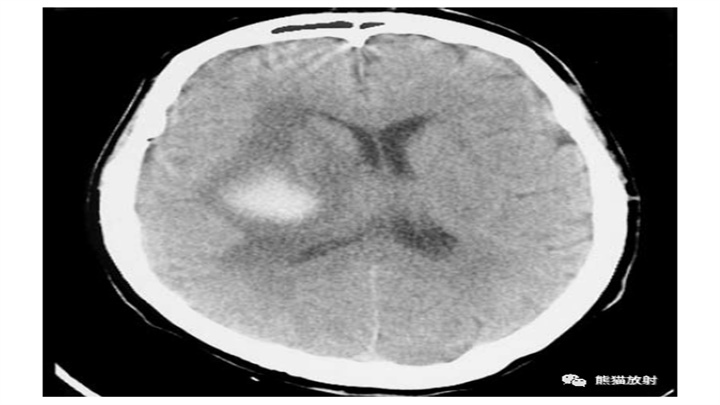

大量脑出血,累及左丘脑和基底节。明显的占位效应(中线结构向对侧明显移位)和脑室积血(同侧脑室变扁,右侧枕角积血)。然而,像往常一样,腹周水肿的数量仅限于周围边界。患者在数小时后死亡。